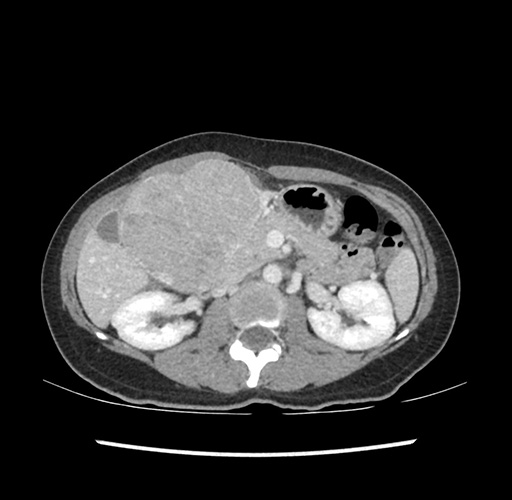

Imaging Analysis

Look through the patient's CT scan to identify any areas of concern for the necessary procedure.

Based on your CT findings, which issue(s) would give reason for "planned slowing down moment(s)" in this case?